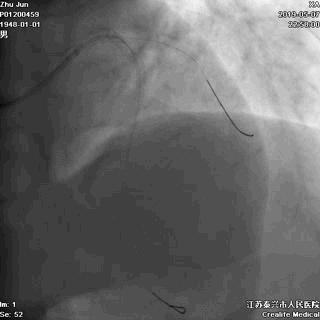

右冠状动脉无严重病变

冠脉左主干线样狭窄

回旋支主支中段闭塞

前降支开口次全闭塞

至此,症状、心电图结合冠状动脉造影检查结果,该患者“急性心肌梗死”诊断明确,冠脉造影提示血栓向主干延伸,病情非常危重,死亡风险极大,需要紧急行心脏介入手术。讲明疾病风险和手术风险后,患方很快接受介入手术。